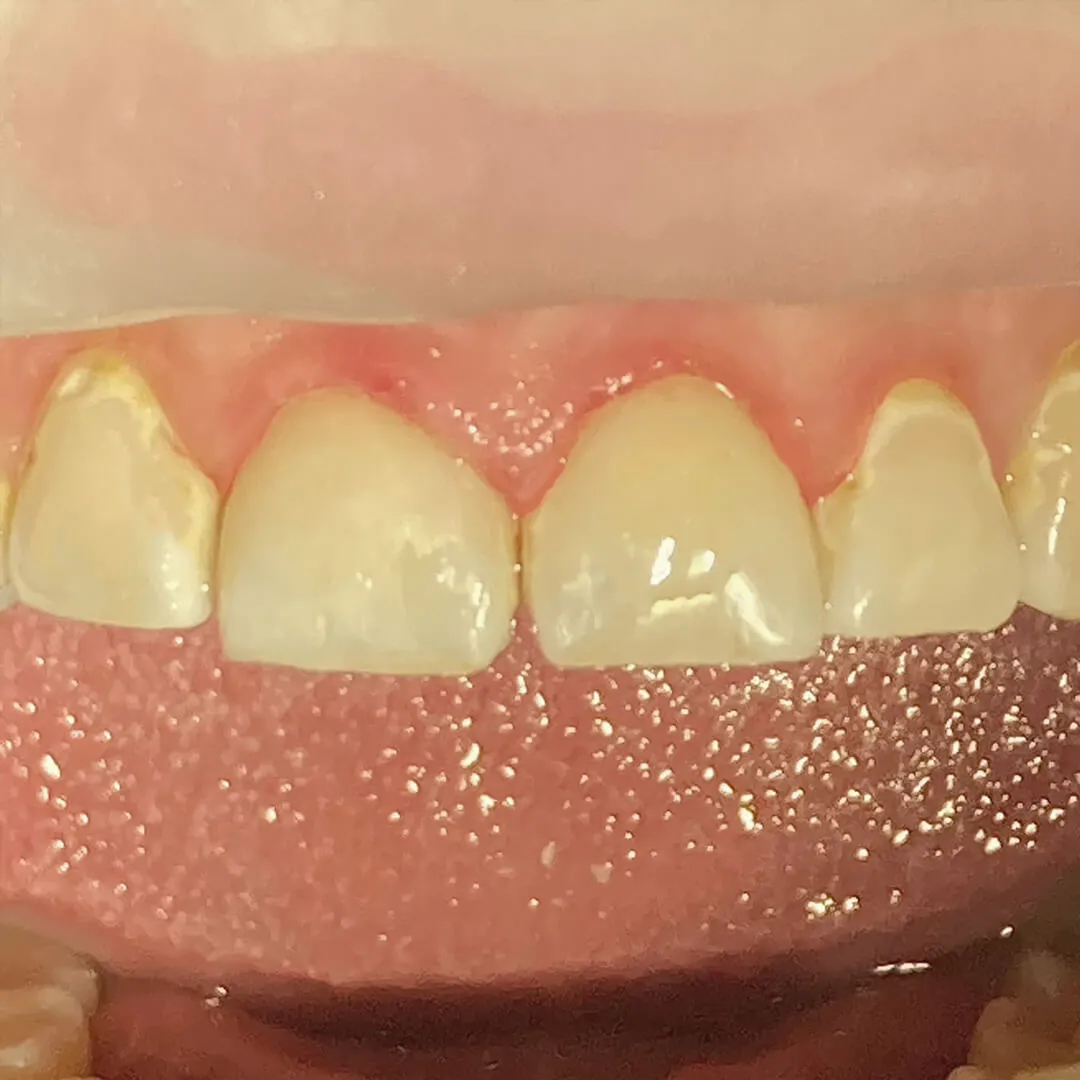

До и после лечения

В «Стоматологию Комфорта» обратился мужчина с жалобами на скол зуба 1.7 и острую боль при надкусывании пищи. Стоматолог-терапевт Серебрякова Мария Борисовна в ходе осмотра полости рта выявила хронический апикальный периодонтит верхнего моляра. Проведено эндодонтическое лечение зуба с временными восстановлением коронковой части. Рекомендована последующая установка постоянной ортопедической конструкции.

- временное восстановление коронковой части зуба 1.7;